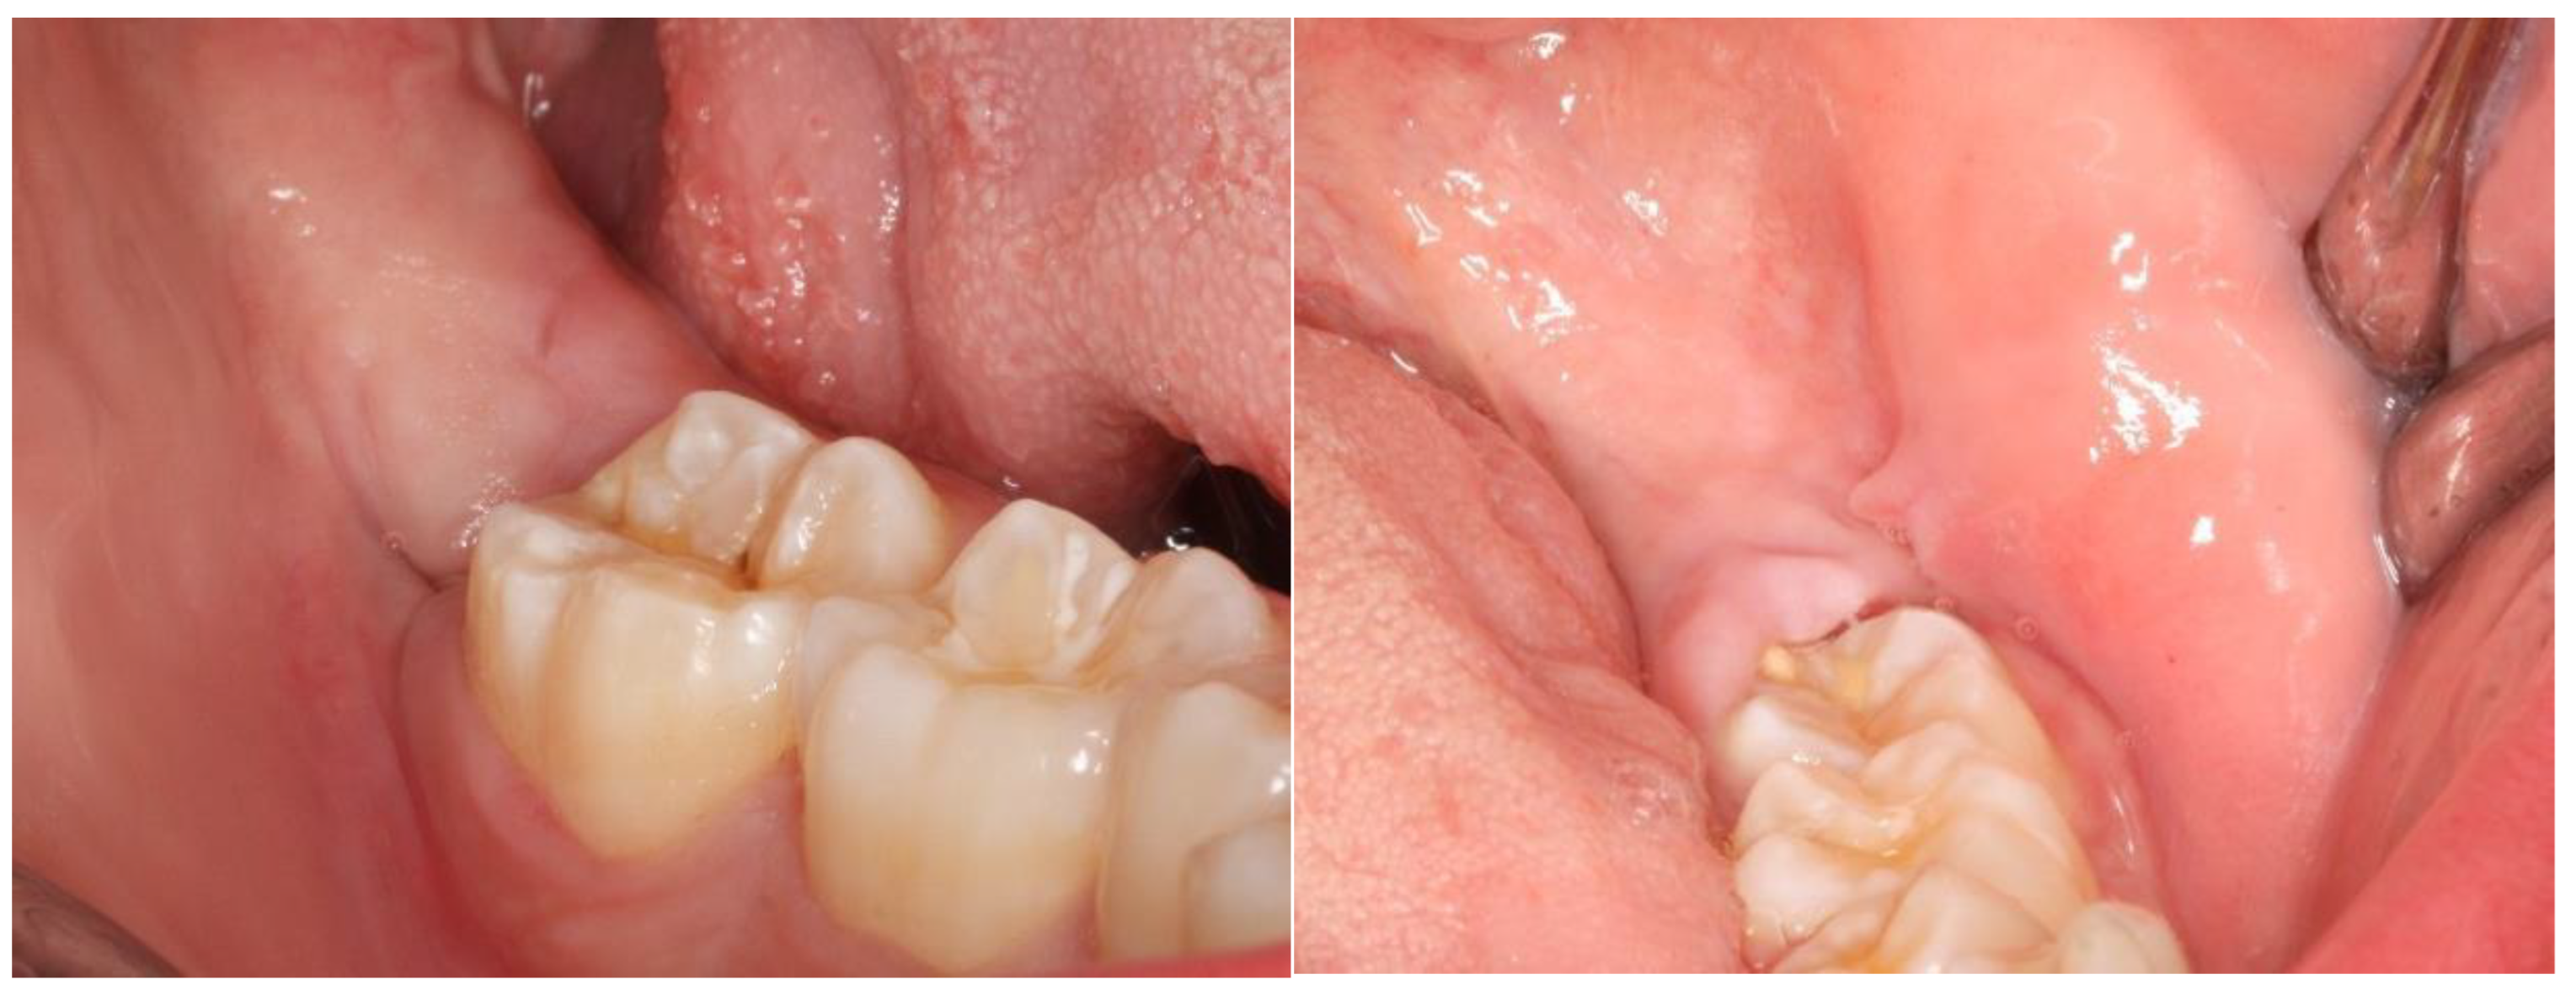

2.2. Definition of the Variables in Study and Follow-Up of Patients

3. Results